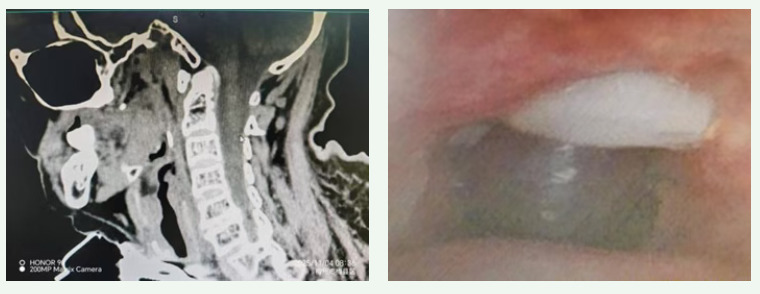

李先主任团队立即对患者进行纤维支气管镜检查,问题出现了:1、声门上黏膜肿胀、声门狭小;2、声门下气切口附近约1cm肉芽肿物伴水肿,导致气道严重狭窄。李先主任立即组织团队讨论,结合患者目前情况,如果贸然行介入消融手术治疗,操作风险高,术中出血几率较高,决定先予激素治疗(于8月19日开始局部注入地塞米松+布地奈德口鼻雾化+甲泼尼龙40mg静滴)+无创辅助通气维持上气道功能。

经过1周治疗后复查纤维支气管镜检查见肉芽水肿明显好转,考虑到患者的实际情况,为解决患者问题,李主任同家属充分交流,拟定替代方案,尝试气道肿物消融,患者家属表示理解,并愿意行消融手术。

8月29日,李先主任带领团队在支气管镜室静脉麻醉+局麻下行介入消融治疗。镜下见气管上段肉芽增生致气管狭窄,几乎完全堵塞。经过2个小时的努力,团队成功完成介入手术,术后气管通畅。

第二关:攻克术后相关组织反复增生

术后第三天,康复医学科团队床边堵管测试,患者气道仍不通畅,患者呼吸困难,遂立即安排纤维支气管镜检查,镜下可见套管上方组织增生,堵塞气道。再次邀请呼吸与危重症医学科李先主任会诊,并再次行介入消融治疗,气道恢复通畅。本以为这次消融术后,患者能成功拔管,结果术后三天,床边堵管测试仍旧不通过,纤维支气管镜镜下仍可见套管上方组织增生。